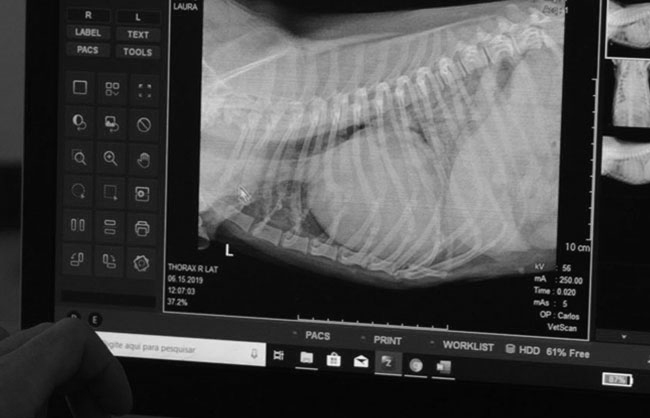

A Vetscan foi a primeira empresa em Curitiba a atuar com duas modalidades de imagem e está há mais de oito anos atendendo em Curitiba e região metropolitana oferecendo o que há de melhor em radiologia e ultrassonografia veterinária.

Os serviços incluem todas as modalidades de exames radiográficos e ultrassonográficos de cães, gatos e equinos, além de biópsias e punções ecoguiadas. Com equipes veterinários e técnicos multidisciplinares e especializados , realizamos diagnósticos por imagem precisos e revisados, exames seriados, exames de controle e planejamentos cirúrgicos.

A Vetscan trabalha 24horas por dia por meio de parcerias e também através de atendimentos agendados, disponibilizando equipes móveis. O principal objetivo é atender de forma dinâmica, fornecendo laudos e imagens no menor tempo possível , por meio de nossas plataformas digitais.